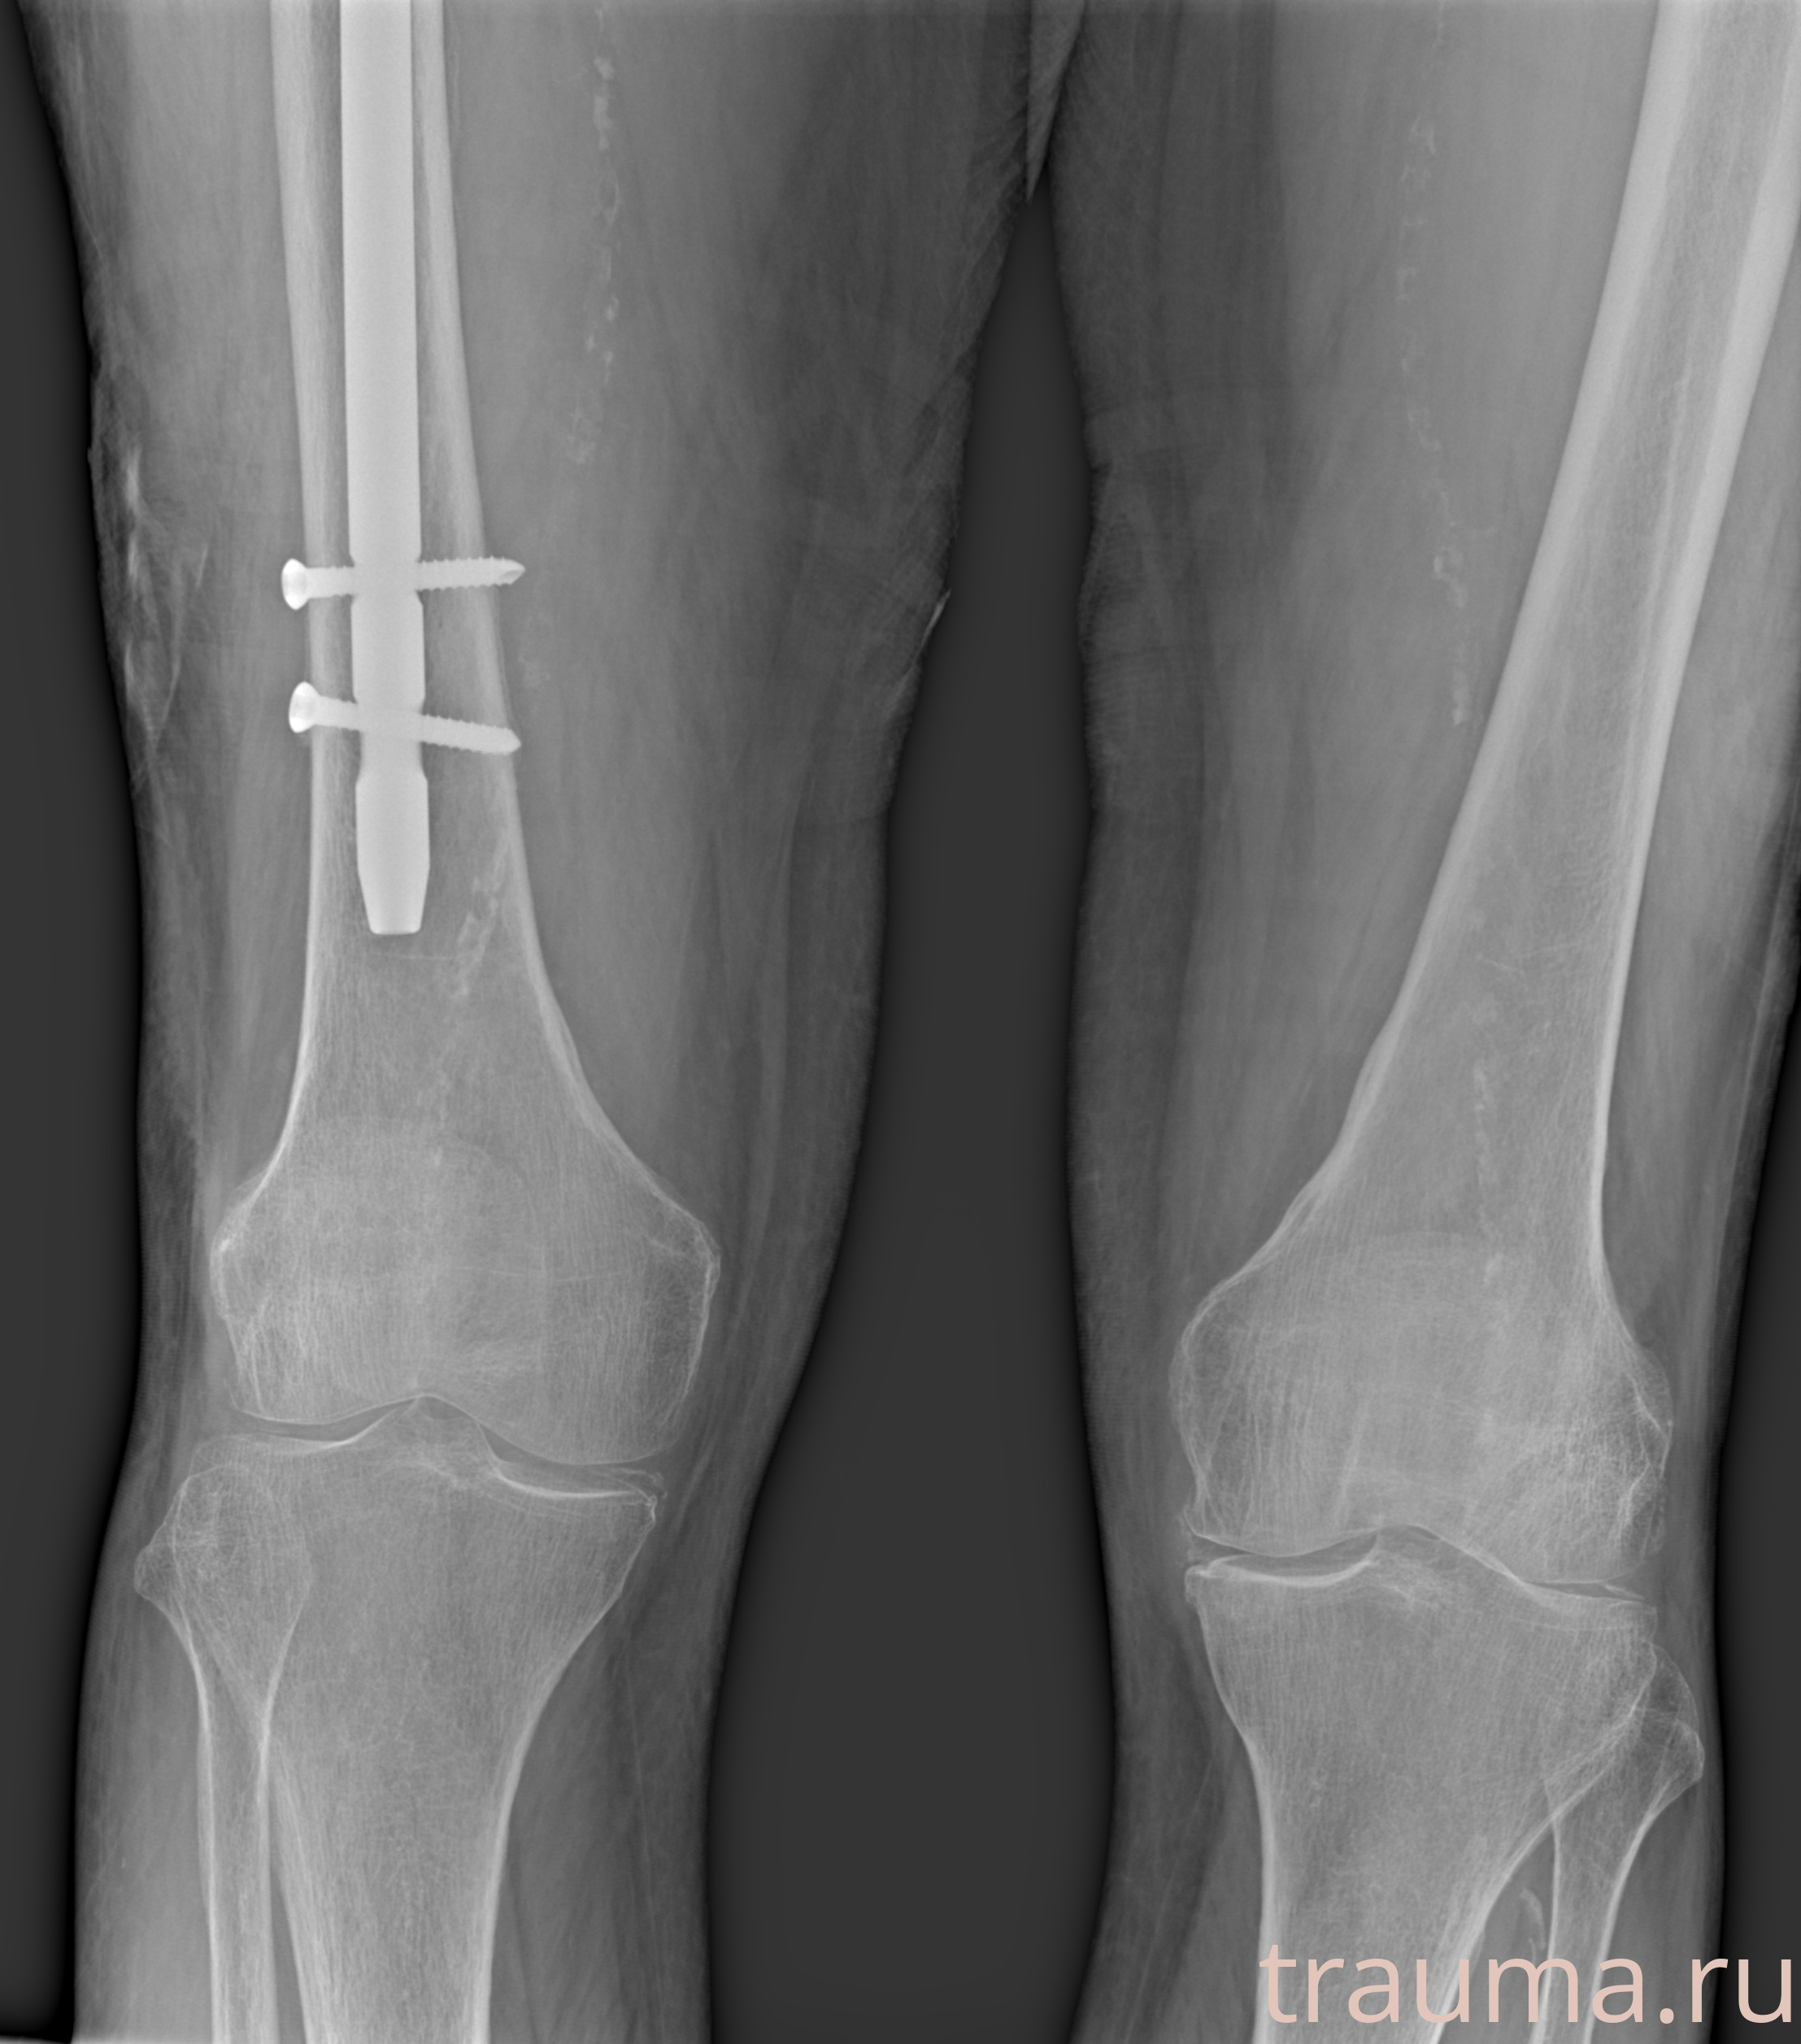

Рентгенограммы